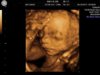

Fanka BB :)